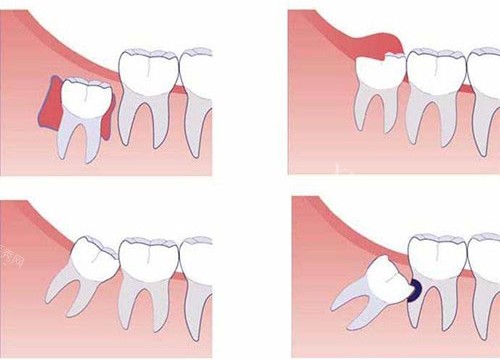

刚进诊所,前台小姐姐就注意到我捂着腮帮子的痛苦表情,赶紧递来冰袋让我冷敷,还优先给我安排了就诊。诊室里的氛围意外温馨,墙上贴着卡通版的牙齿科普漫画,牙椅旁边甚至放着个小玩偶,让我原本紧张到嗓子眼的心稍稍放下。接诊的赵医生拿着口镜检查时特别温柔,发现我的智齿是横着长的阻生齿,卡在牙槽骨里,难怪疼,他调出我的口腔 CT 影像,用手机上的 3D 模型给我演示拔牙过程,哪里需要切开牙龈、哪里要小心避开神经,讲得明明白白,还说会尽量减少创伤,术后修复更快。

拔牙前,护士小姐姐帮我量血压、测凝血功能,反复确认我没有过敏史,还贴心地给我披上小毯子。打麻药时,我攥紧了手心,赵医生却像哄小孩似的安慰我:“就像被蚂蚁叮一下,数到三就不疼啦!” 没想到真如他所说,麻药起效后,除了感觉牙齿被轻轻晃动,全程几乎没有痛感。赵医生手法特别稳,先用工具小心分离牙龈,再精细地把智齿分成小块取出,整个过程干净利落,还时不时问我有没有不舒服。原本以为至少要折腾半小时,结果不到 15 分钟就结束了,我甚至都没反应过来。